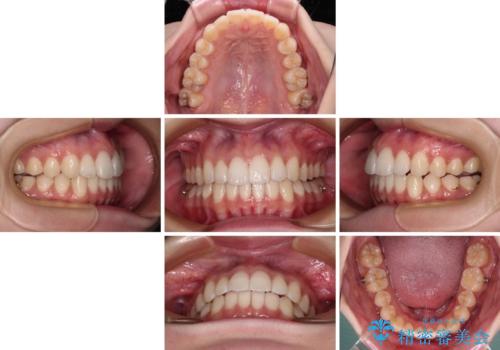

インビザラインによる上下歯列の側方拡大と後方移動、必要に応じてIPR(歯と歯の間を削る)によりスペースの獲得により歯列を整えることとしました。

治療途中、出産や転居があり、2年ほど治療期間が長くなってしまいましたが、前歯の歯並びや飛び出した感覚を無事に改善させることができました。